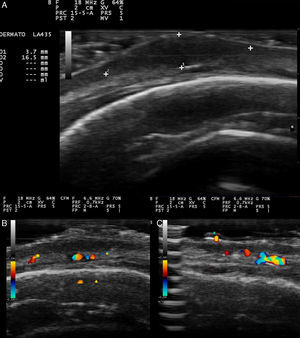

Se realizó una ecografía (sonda 18MHz, eSaote MyLab25Gold) que en modo B mostró un nódulo predominantemente hipoecoico de 3,7mm×16,5mm y bordes bien definidos localizado en la dermis profunda y en el tejido celular subcutáneo (fig. 2A). La periferia de la lesión presentaba una ecogenicidad mixta en contraste con la zona central, más hipoecoica. En la parte inferior se observó una zona hiperecogénica que podría corresponderse con un refuerzo posterior. La epidermis aparecía como una banda hiperecoica. La lesión se extendía en el plano horizontal de forma difusa, siendo más difícil la identificación de sus límites en ese plano (figs. 2B y C). Así mismo, en los bordes laterales de la lesión y en las zonas no nodulares de la neoformación predominaba la ecogenicidad mixta sobre las zonas hipoecoicas. El Doppler color mostraba una neovascularización asimétrica e irregular en la periferia de la lesión (figs. 2B y C).

A. Nódulo hipoecoico de bordes bien definidos donde los bordes son de una ecogenicidad ligeramente superior al centro. B. El doppler color mostraba un aumento de la vascularización y vasos de mediano calibre asimétricamente distribuidos en la base del nódulo. C. Aumento de la vascularización en la zona no nodular de la lesión.